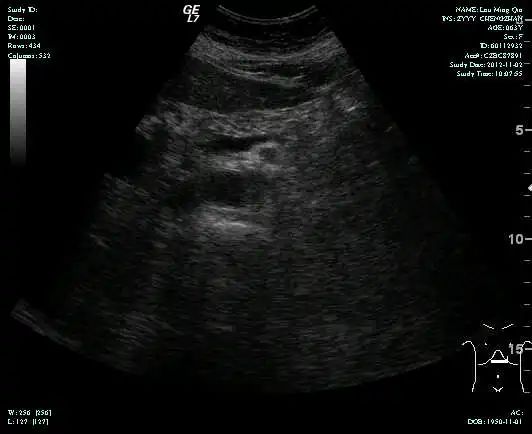

• MR示:

MR-H1

• 第三次FOLFOX+T方案后 B超提示肝转移灶消失